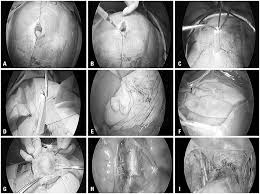

Most ovarian cysts disappear naturally; A follicular ovarian cyst, if the egg is not ejected and the amount of fluid continues to increase, can reach sizes of up to 10 cm. Using a laparoscope — a slim, lighted instrument inserted into your abdomen through a small incision — your doctor can see your ovaries and remove the ovarian cyst. In a small minority of cases, cysts can be cancerous. I was diagnosed as having a 9.1 cm ovarian cyst in my right ovary two days ago.

Using a laparoscope — a slim, lighted instrument inserted into your abdomen through a small incision — your doctor can see your ovaries and remove the ovarian cyst.